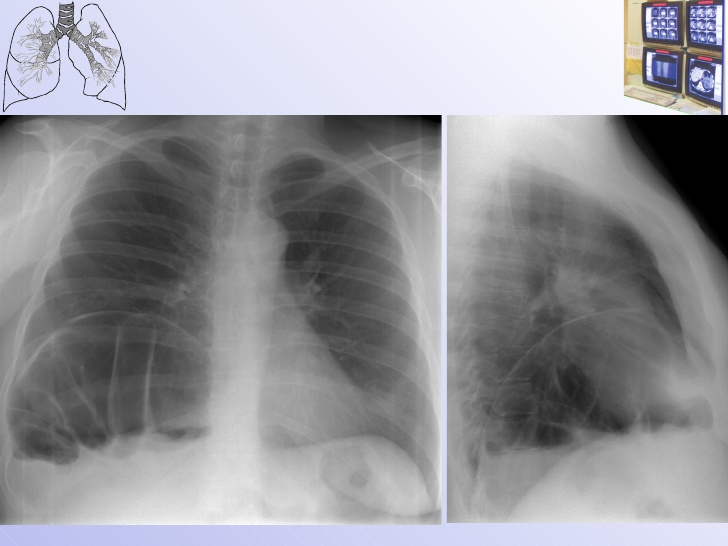

Рентгенография небного шва: Медицинские исследования и диагностика